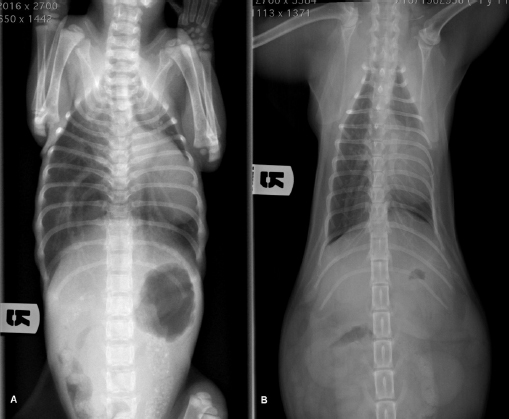

Radiographic examination revealed severe dorsal displacement from the fifth sternebra to the xiphoid cartilage and a dorsal displacement of the cardiac silhouette on the lateral view (Fig. 1A), and a left mediastinal shift and compression of the left pulmonary lobes on the ventrodorsal view (Fig. 2A). VI and FSI were measured on the radiographs, being 3.2 and 9.1, respectively. The authors decided to measure these two indices also at the level of T9 because this vertebra corresponded to the point of minimum height of the thorax. VI and FSI at the level of T9 were 2.3 and 15.2, respectively. The authors measured also the minimum thoracic height (MinTH) that resulted 4.3 mm, at the level of the last sternebra.

Fig. 1. Left lateral radiographic view of the thorax of the cat with pectus excavatum. Comparison of patient’s thorax before (A) and after (B) surgical treatment at 9 months postoperatively.

Fig. 2. Ventrodorsal radiographic view of the thorax of the cat with pectus excavatum. Comparison of patient’s thorax before (A) and after (B) surgical treatment at 9 months postoperatively.

Radiographs were obtained as previously described at each follow-up examination (Figs. 1B and 2B). IV, FSI, and MinTH were calculated and the values are reported in Table 1.

Four months postoperatively the kitten increased her body weight from 550 to 2,436 g and the skeletal deformity was dramatically improved at physical examination. No episodes of dyspnea or exercise intolerance were noticed by the owner. The VI and FSI measured on the radiographs obtained 4 months after surgery were 10.2 and 2.0, respectively. The same indexes measured at the level of T9 were 8.8 and 2.3, respectively, and MinTH was 21 mm.

Nine months postoperatively the cat underwent an ovariohysterectomy with no anesthetic-related complications. The cat was discharged from hospital 6 hours postoperatively and recovered uneventfully. Radiographs were obtained as previously described before the surgery. VI and FSI resulted in 12.4 and 1.5, respectively; the same indexes measured at the level of T9 were 9.4 and 2.1, respectively, and MinTH was 26 mm.